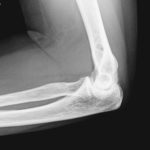

- Röntgenbild Ellenbogen

- Röntgen Ellenbogen seitlich